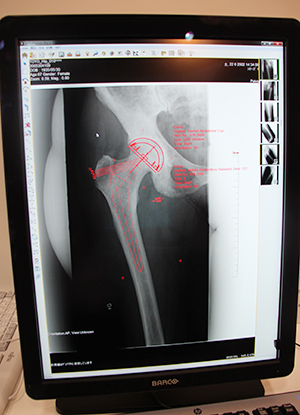

東陽テクニカはバージョンアップした整形外科デジタルプランニングツール“OrthoPlanner Pro”を展示した。今回は正面と側面の画像を同時に確認しながら,連動させて作業できる左右連動機能と,部位ごとに組み合わせていたインプラントのテンプレートをパッケージすることができるキット作成機能が追加された。これにより,さらに操作性が上がり,効率の向上が期待できる。

キット作成機能でステムとカップをパッケージした新しいテンプレート。骨のサイズを認識して,インプラントのサイズも自動で算出されている。